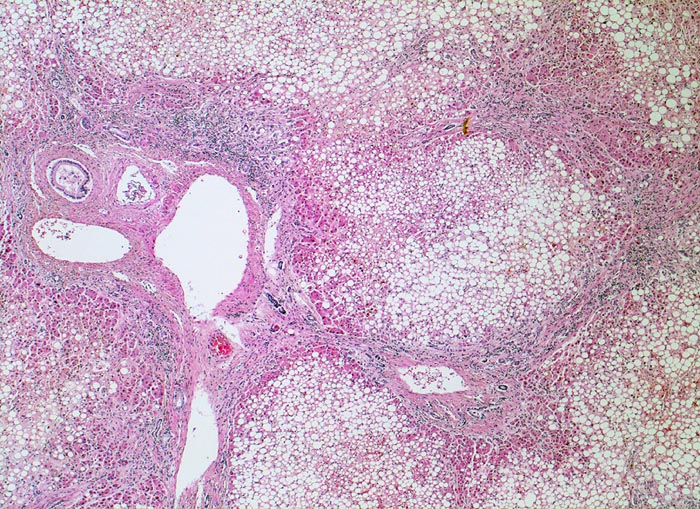

• Vollständiger feinknotiger zirrhotischer Umbau.

• Gemischtes portales, septales und intralobuläres Entzündungsinfiltrat.

• Canaliculäre Cholestase in einem Zirrhoseknoten.